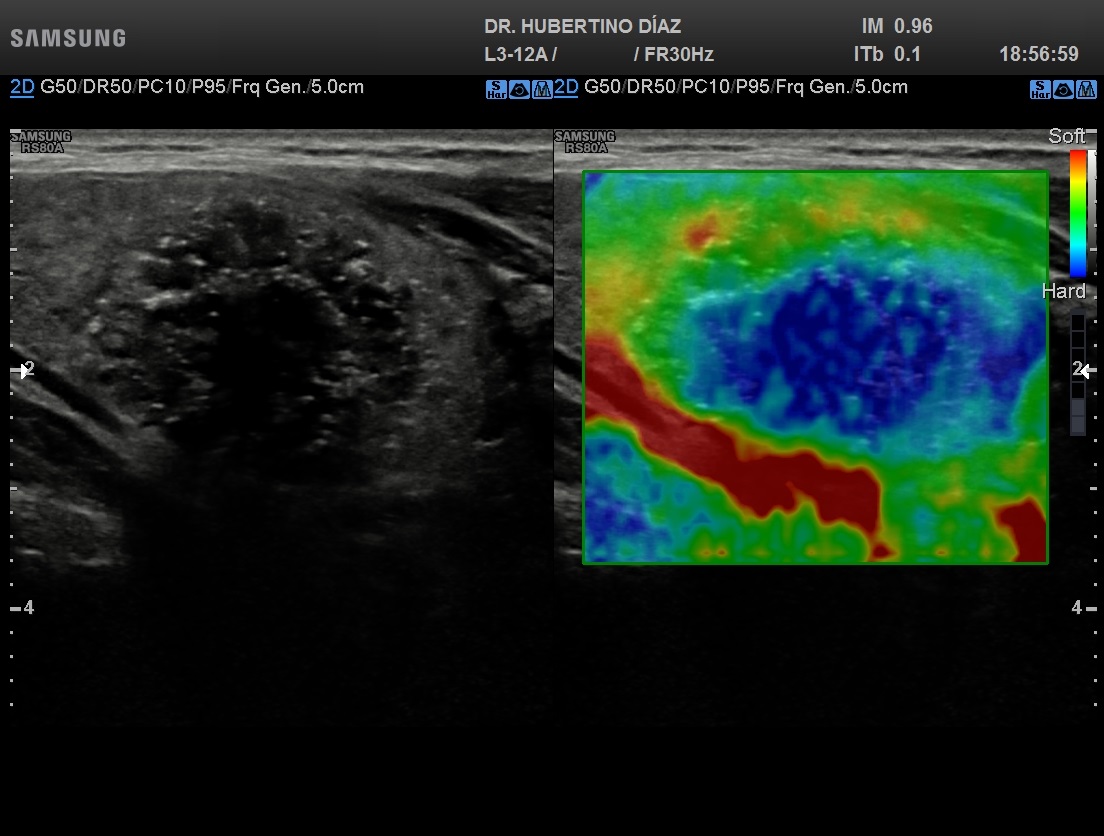

Drenaje y alcoholización con guía ecográfica (esclerosis)

El tratamiento de quistes tiroideos en Lima mediante drenaje y esclerosis con alcohol (alcoholización) guiado por ecografía es una alternativa moderna, segura y mínimamente invasiva para manejar quistes tiroideos sintomáticos o recurrentes. En Diagnoimagen - Dr. Hubertino Díaz, realizamos este procedimiento con tecnología de alta resolución y control ecográfico en tiempo real, garantizando máxima precisión y seguridad.

El procedimiento consiste en aspirar el contenido del quiste y posteriormente aplicar una pequeña cantidad de alcohol para producir su esclerosis, logrando la reducción o desaparición  del quiste y evitando su reaparición. Es una excelente opción para pacientes que desean evitar cirugía, especialmente en quistes benignos confirmados.